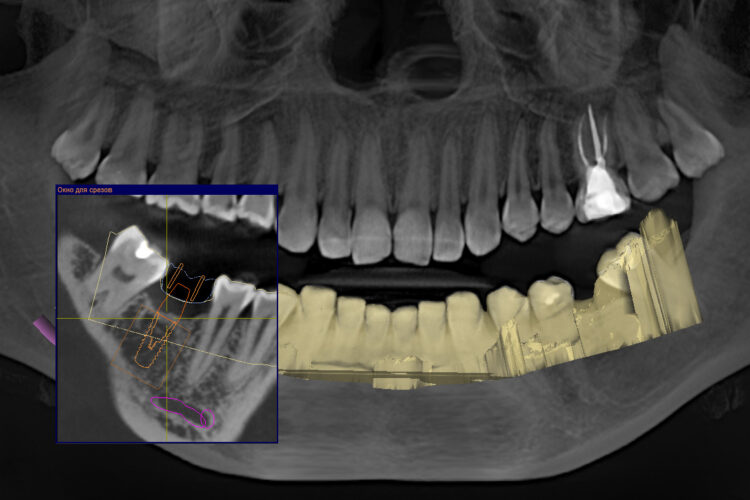

- Рентгенодиагностика. Ранее она включала в себя прицельный рентгеновский снимок или ортопантомограмму. Минус этих снимков заключается в том, что у них есть погрешность до 8 мм, то есть на панорамном снимке, если мы берем анатомические образования (нижнечелюстной нерв, гайморову пазуху) мы не сможем правильно подобрать имплантат и соответственно правильно спланировать такую операцию. При появлении компьютерной томографии у нас погрешность (в зависимости от томографа) в среднем 1 мм. И этот один миллиметр позволяет нам спланировать качественную имплантацию. В современных компьютерных томографах мы можем подобрать по специальной базе имплантатов имплантат любой длинны и диаметра, любого производителя.

При помощи диагностического аппарата (компьютерный томограф) мы изучаем толщину кости, плотность кости и определяем, будем ли использовать костную пластику.